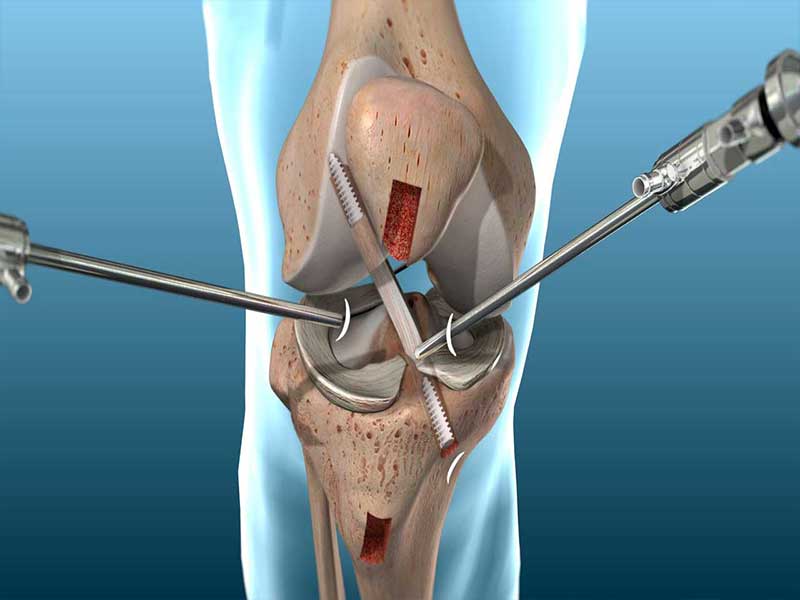

Dr. Amit Meena is a specialized center dedicated to treating complex knee problems, offering top-quality, research-backed joint replacement and sports medicine treatments. Because we focus exclusively on these specific medical areas, we have developed exceptional expertise and built a strong reputation for excellence both in India and around the world. Dr. Amit Meena is a specialized center dedicated to treating complex knee problems, offering top-quality, research-backed joint replacement and sports medicine treatments. Because we focus exclusively on these specific medical areas, we have developed exceptional expertise and built a strong reputation for excellence both in India and around the world.